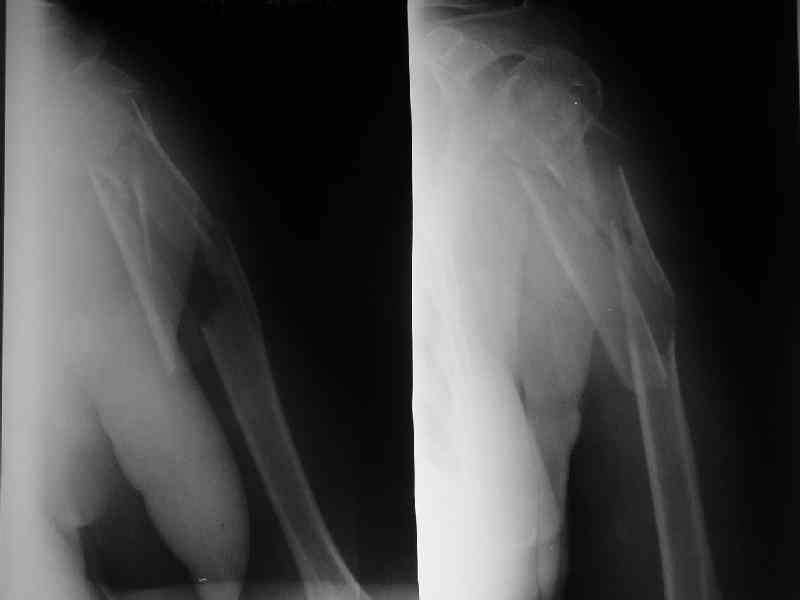

Здесь нет необходимости в серкляже. Вмешиваться на промежуточных отломках приходится, если есть угроза перфорации кожи, или промежуточный отломок попал в фасцию, как пуговица в петлю. В приложении сегментарный оскольчатый перелом плеча в проксимальном отделе, фиксированный больщеберцовым стержнем. Как видите, обошлось без серкляжа. Функция полная.